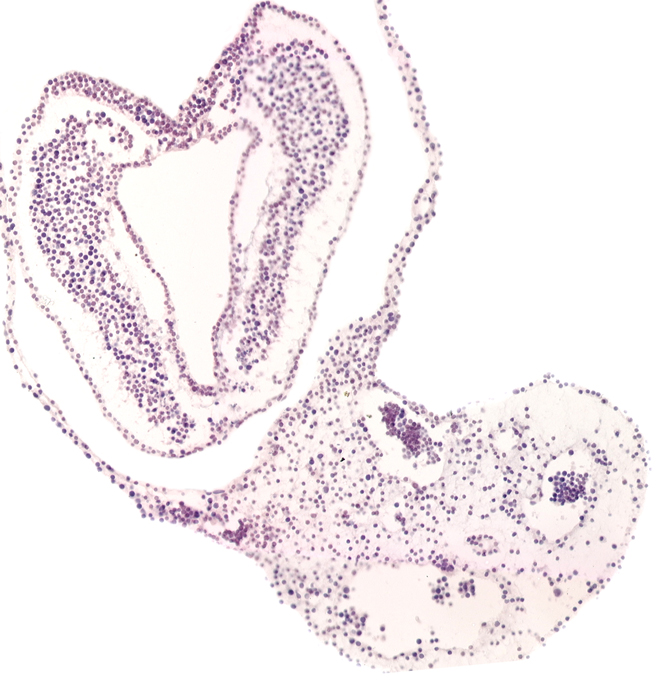

Carnegie Embryo #3709 | Location: 02-03-04

Keywords: left umbilical artery, left umbilical vein, notochordal (primitive) pit, right umbilical artery, right umbilical vein, tail fold region

Source: The Virtual Human Embryo.